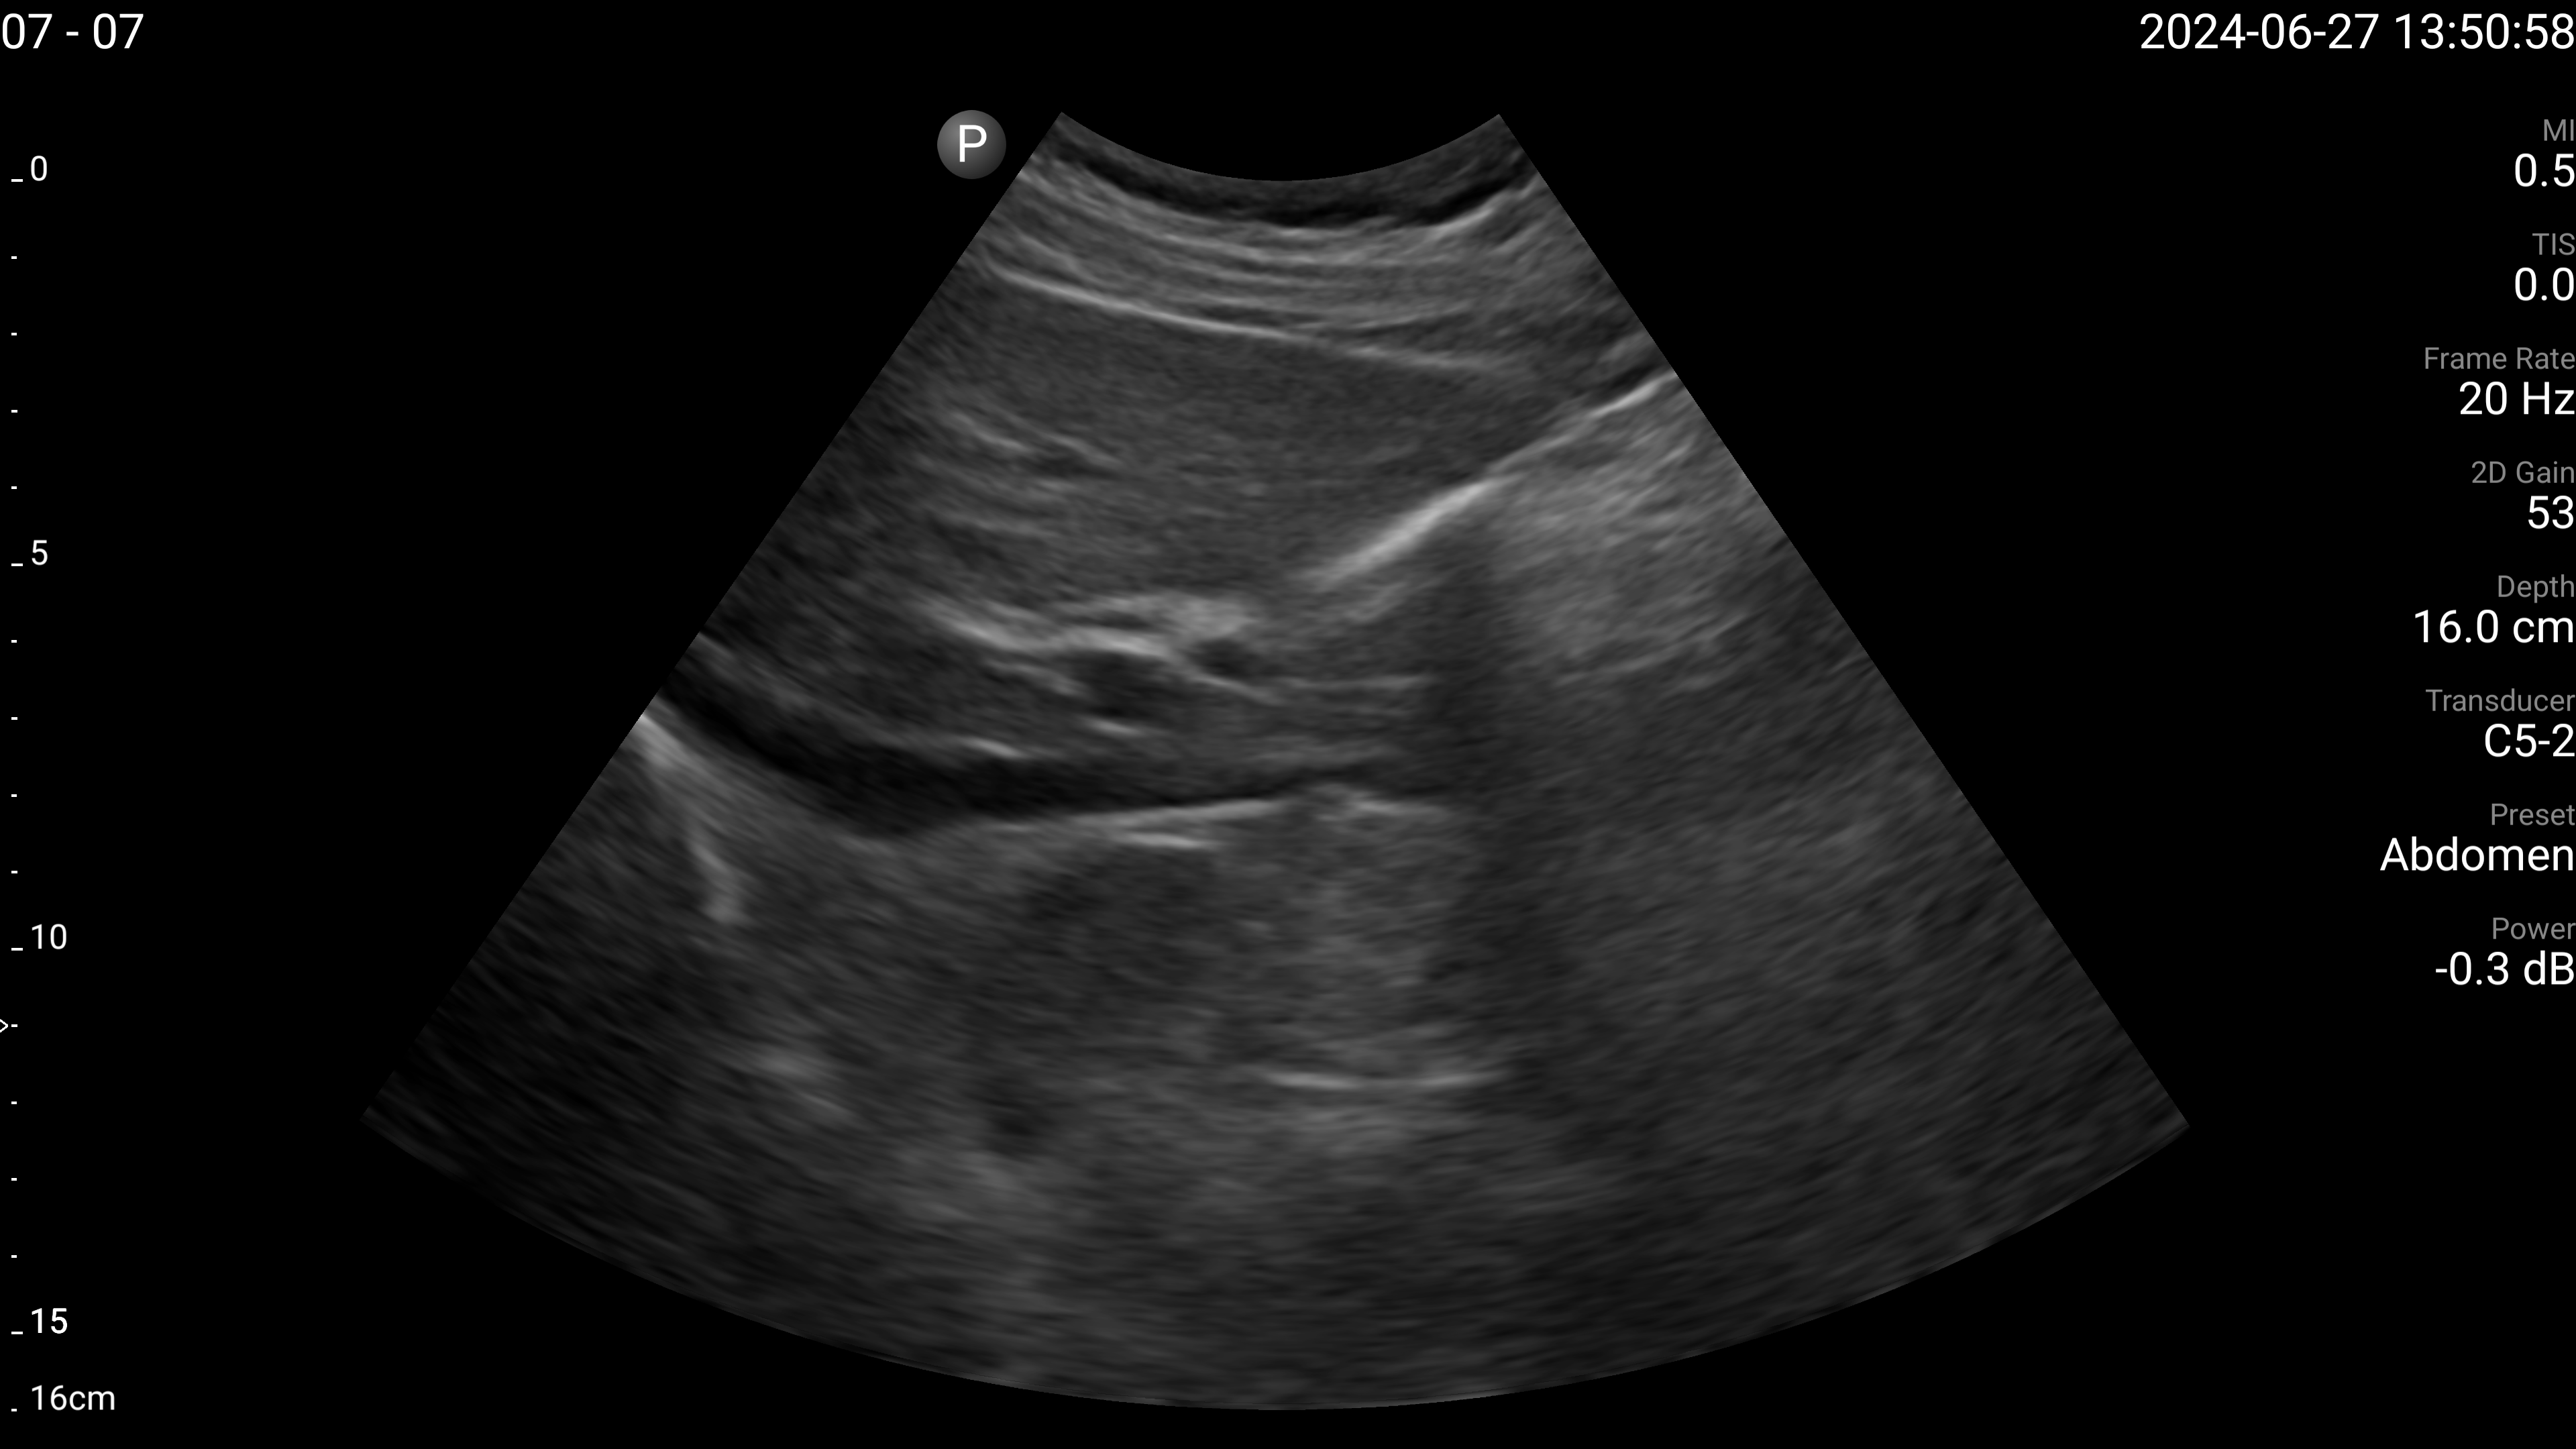

Refer to caption

(a) Proximal aorta with AP diameter.

(b) IVC - longitudinal.

(c) Left lobe of liver - long axis.

(d) Left lobe of liver - transverse.

(e) Right portal vein - transverse.

Figure 4: Examples of the target US images acquired by the sonographers using the human teleoperation system.

The sonographers completed 11 abdominal US scans, each with 5 target images and measurements for a total of 55 images. An example image of each of the targets acquired during these tests is shown in Fig. 4. After completing the scans, two radiologists scored the images based on quality, including identifying targets that could not be seen or were not captured (which were given a score of 0). The distribution of these scores is illustrated in Fig. 5. The first radiologist identified 4 out of the 55 targets as not visible, while the second radiologist identified 6 out of 55 as not visible. Combined, this accounted for 7 unique targets that at least one radiologist considered missing. Of these missing targets, three were not captured due to large amounts of bowel gas and body habitus while one was seen but the sonographer did not capture and save the image. When excluding all the missing targets, the images obtained a mean score of 4.28±0.95plus-or-minus4.280.954.28\pm 0.95 out of 5 and 91.7% of the images were scored 3 or higher by both radiologists. A score of 3 or higher indicated the image quality was sufficient for basic image interpretation. 31.3% of the images were scored 5 by both radiologists, indicating the image quality was good and meaningful image interpretation was easy.